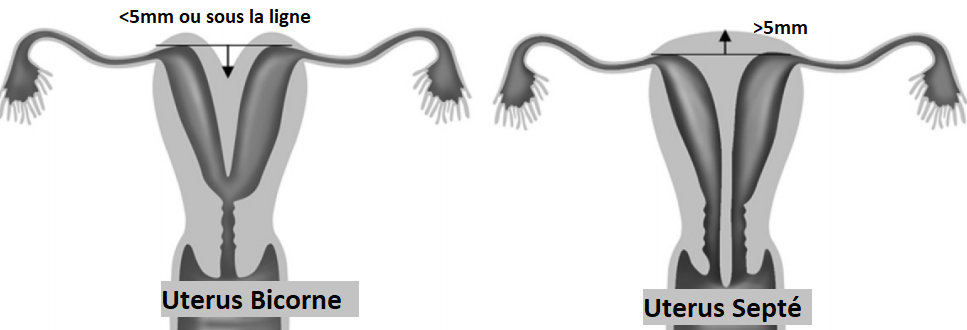

Utérus Bicorne

Uterus Septé

Bicorne VS Septé